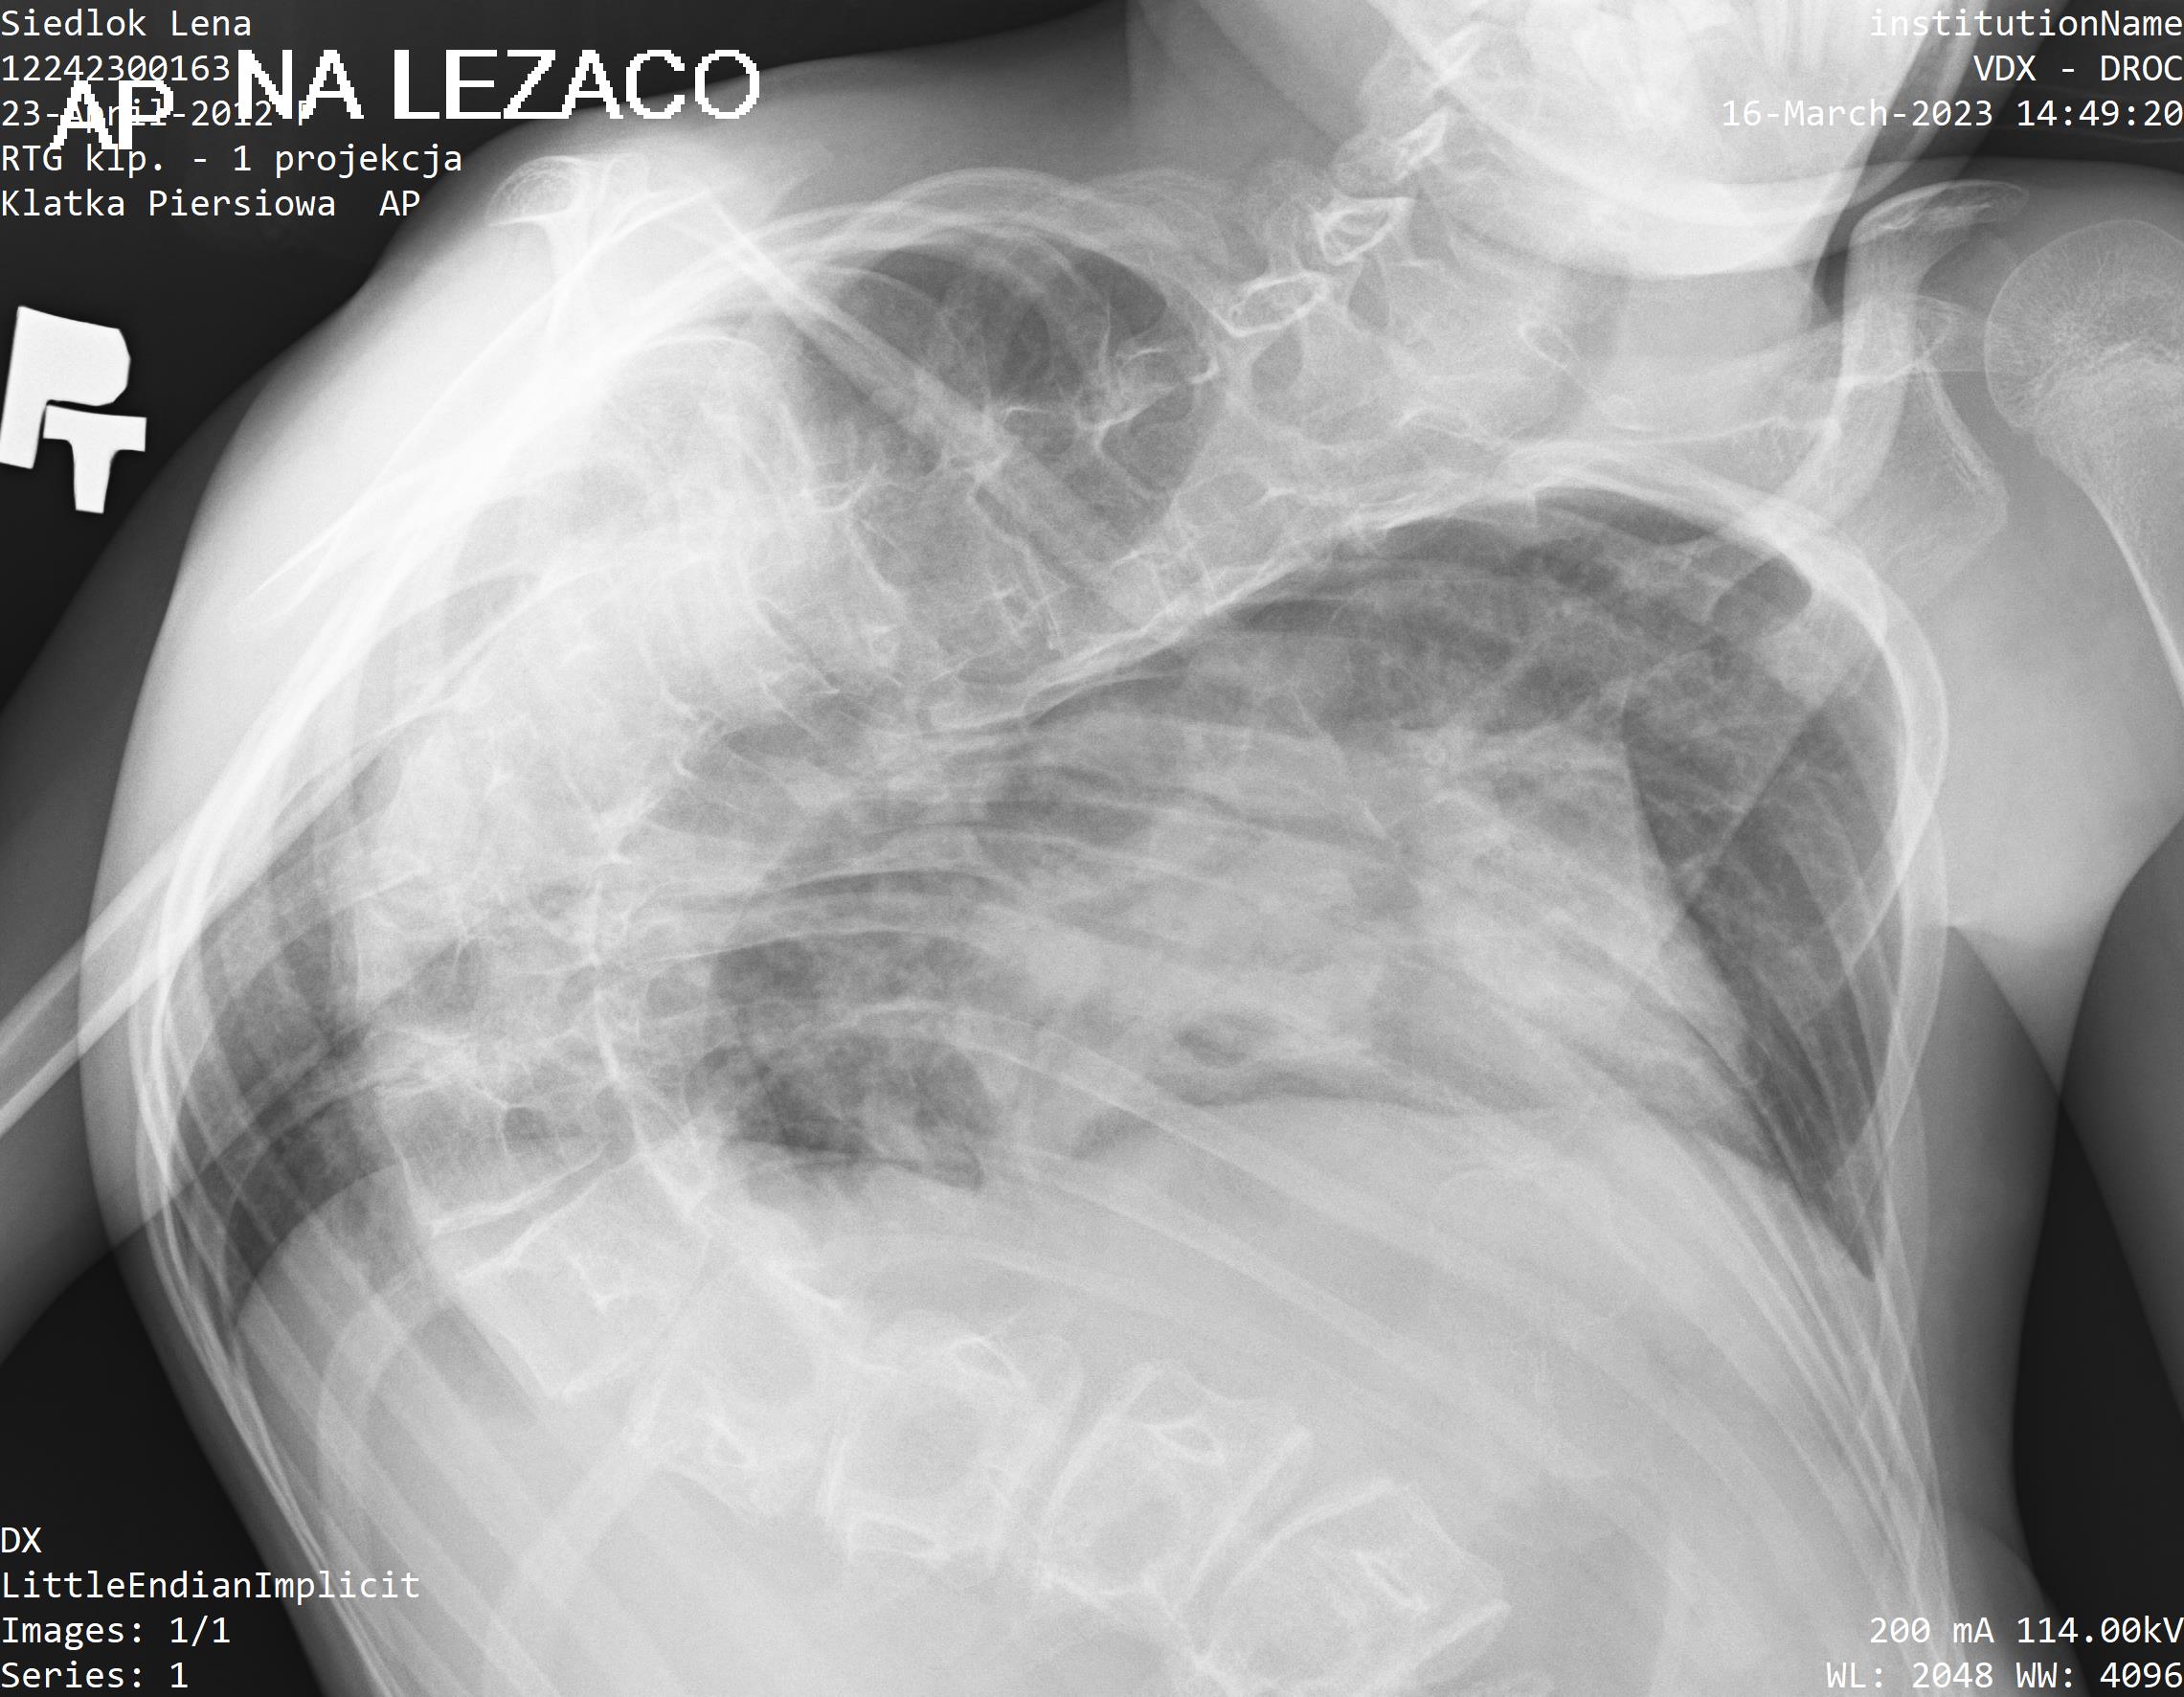

Pewnie poradzilibyśmy sobie, gdyby nie pojawiła się kolejna trudność. U Leny postępuje skolioza porażenna, która odpowiada za powstanie dużego garba na jej plecach! To nie wszystko. Skolioza sprawia, że bardzo często choruje na zapalenie płuc i oskrzeli. Nie są to epizody, tylko cyklicznie nawracające choroby!